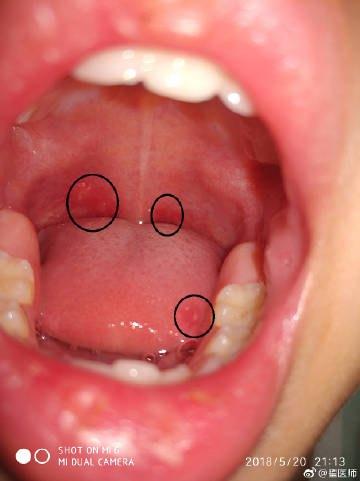

每天用10秒法检查孩子舌苔和口气的时候,加一个动作——查看孩子咽喉部。如果孩子当天咽喉部很红肿,那么就要尽快干预。如果发现白色的小点或者溃疡点,同时孩子有些发热的表现,那么也要马上干预用药。